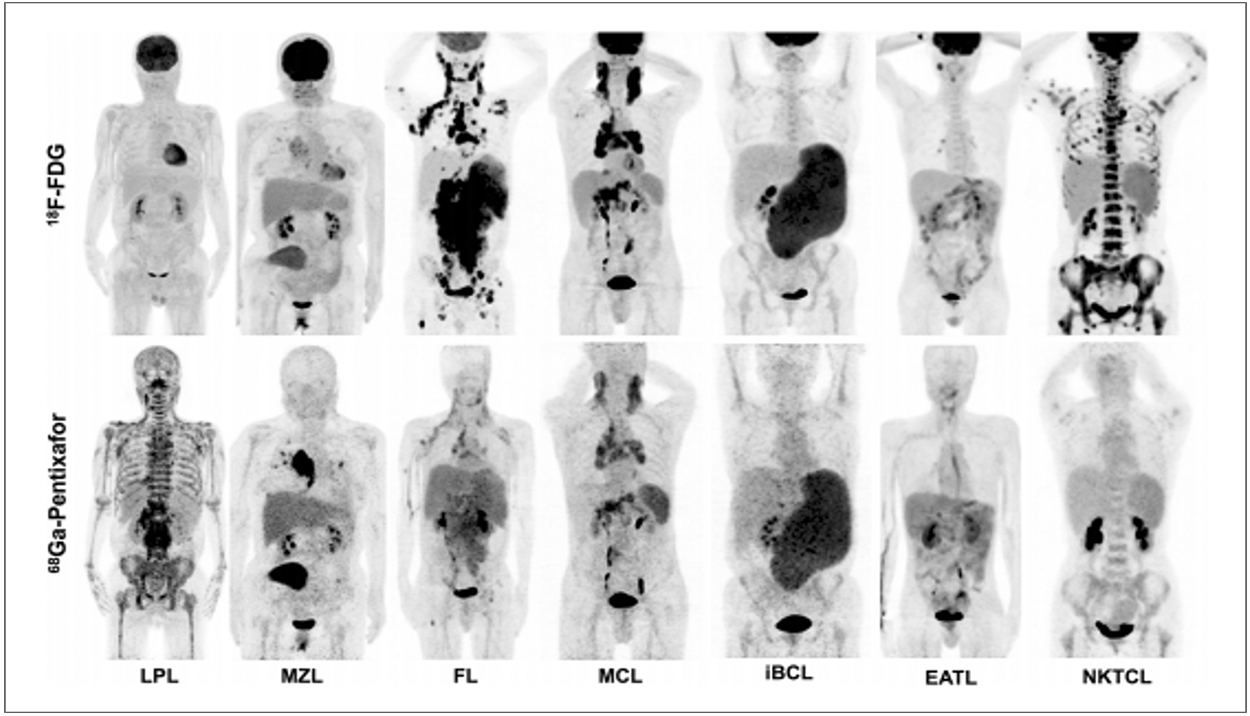

Chemokine receptor -4 targeted PET/CT with68Ga-Pentixa for in assessment of newly diagnosed multiple myeloma:comparison to 18F-FDG PET/CT

Qing qing Pan · Xinxin Cao · Yaping Luo · Jian Li ·JunFeng · FangLi